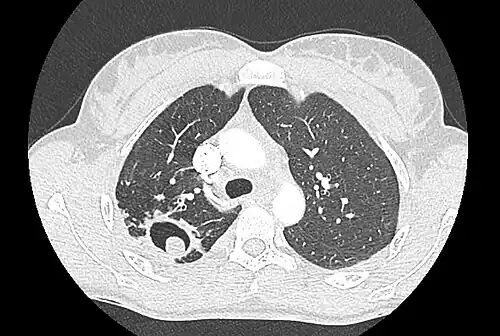

Sur la radiographie pulmonaire, un aspergillome simple apparaît comme un nodule dense, le plus souvent entouré d'un croissant aérique[11]. La radiographie seule ne suffit pas au diagnostic ; un scanner est recommandé[29]. Sur le scanner thoracique, le centre de la cavité est occupé par l'aspergillome[58]. La pseudo-tumeur bouge dans la cavité lorsque le patient change de position (signe de Monod)[58]. Dans l'aspergillome simple, il n'y a pas d'évolution entre les examens et la paroi de la cavité est le plus souvent fine[13]. Un aspergillome complexe[13] présente en revanche l'aspect d'une cavité (ou plusieurs) à parois épaisses, comportant en son centre une truffe aspergillaire. Il existe parfois un début de fibrose pulmonaire[59]. La plèvre adjacente a également un aspect fibrosé, et l'évolution radiologique est lente, mais toujours vers l'aggravation[13]. Un halo en verre dépoli peut également entourer les lésions[45].

- Aspect scannographique typique d'un aspergillome développé dans une caverne tuberculeuse.

- Le changement de position modifie la position du grelot aspergillaire dans la cavité (signe de Monod).

Le diagnostic radiologique seul n'est cependant pas adapté, d'autres lésions pouvant avoir une présentation similaire (cancer pulmonaire excavé[60],[14] notamment, mais aussi abcès pulmonaire et kyste hydatique[14]). L'injection de produit de contraste iodé, dans le but de mieux visualiser les vaisseaux, permet de dépister un anévrysme de Rasmussen[61], une dilatation pseudo-anévrysmale de l'artère pulmonaire au voisinage d'une cavité intrapulmonaire à risque de rupture, qui entraîne alors une hémoptysie massive souvent fatale[62].